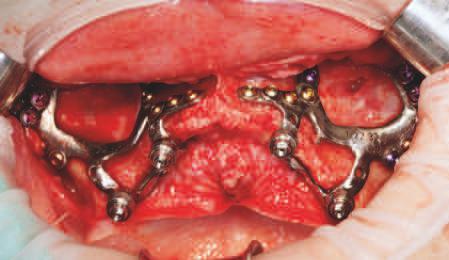

Implantur le subper ostale sunt structur metal ce fabr cate nd vdual pentru a se adapta ș a restab l zonele edentate. Personal zate ș concepute pentru a se potr v morfolog e osoase un ce a pac entulu , mplantur le subper ostale sunt plasate sub per ost ș sunt stab l zate pr n șurubur de f xare care ntră în contact cu osul sub acent ș țesutul f bros care le acoperă. Spre deoseb re de mplantur le convenț onale, mplantur le subper ostale se sprj nă d rect pe os ș prez ntă bontur care emerg pr n țesutur le g ng vale pentru a acomoda proteze f xe sau detașab le totale sau parț ale (un exemplu de implant subperiostal individualizat este ilustrat în fig. 6-14)

Protocolul debutează cu scanarea anatom e osoase a pac entulu folos nd tehnolog a CBCT, ar datele sunt ut l zate pentru o reconstrucț e v rtuală a max larulu edentat. Acestea sunt apo comb nate cu nformaț le d n scanăr le ntraorale ș modelele de ceară d agnost ce pentru a produce un model v rtual 3D cu scopul de a plan f ca corect des gnul mplantulu ș al proteze . Implantur le subper ostale moderne sunt de ob ce fabr cate pr n s nter zarea d rectă a metalulu cu laser (direct metal laser sintering, DMLS), proces în cadrul căru a un laser de

mare putere este ut l zat pentru a top pulber le metal ce strat cu strat. Totodată, se fabr că ș o repl că a mplantulu d n mater al răș n c, astfel încât cl n c anul să poată plan f ca corespunzător ntervenț a ch rurg cală în ceea ce pr vește locaț le structur lor anatom ce v tale ș des gnul adecvat al lamboulu .

În z ua nserăr , după ce s-a real zat o expunere suf c entă a suportur lor anatom ce sub acente, mplantul este ver f cat în pr v nța adaptăr corecte, ar or ce mod f căr necesare sunt efectuate îna nte de plasarea f nală. Implantul este stab l zat pe poz ț e cu șurubur monocort cale nserate pr n găur predef n te în osul sub acent. Lamboul este decolat ș d secat corespunzător pentru a obț ne suf c entă pas v tate care să as gure o înch dere pr n ntenț e prmară în jurul bontur lor expuse ale mplantur lor. După per oada necesară de v ndecare, se au amprentele corespunzătoare pentru fabr carea ș l vrarea proteze f nale.